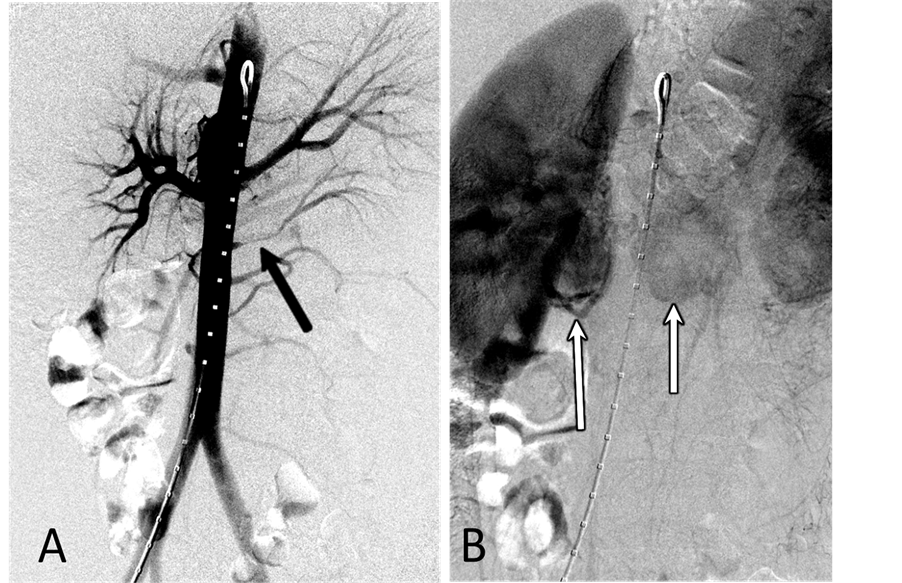

With the patient under general anesthesia, a 5-Fr Omni Flush catheter (Angio Dynamics, Queensbury, NY, USA) was placed in the aorta above the celiac axis from a percutaneous retrograde transfemoral arterial approach, and aortograms were performed, first with 30 cc of CO2 and then in the anterior-posterior (AP) and left anterior-oblique (LAO) projections with Visipaque (GE Healthcare, Cork, Ireland, UK). During each of the runs, there was a moderate increase in blood pressure from baseline systolic pressures of 120 s to 145 - 150 s, lasting 5 minutes, accompanied by bradycardia and transient arrhythmia. A nitroglycerin drip was started; however, the patient did not require any alpha or beta blockers. Next, a 5-Fr shepherd hook catheter (Angio Dynamics, Queensbury, NY, USA) was positioned and digital subtraction angiography (DSA) was performed, sequentially, in the right and left renal arteries, superior mesenteric artery, and finally the celiac axis. The aortograms revealed two vascular retroperitoneal tumors to the right and left of the aorta, at the level of L1-2, measuring 22 mm × 27 mm and 26 mm × 27 mm, respectively (Figure 2(A) and Figure 2(B)). The right retroperitoneal mass was located posteroinferior to the right renal artery and posterior to the inferior vena cava (IVC). The left retroperitoneal mass was located between the left main renal artery and the inferior accessory renal artery. The inferior accessory renal artery supplying the lower pole of left kidney showed diffuse narrowing due to either compression or catecholamine release by the tumor (Figure 3(A) and Figure 3(B)). Subsequently, bilateral renal arteriograms were performed without a hypertensive response to the injection of contrast material. The right main renal artery was displaced by the tumor with mild arterial narrowing (Figure 4(A) and Figure 4(B)). Left renal arteriogram showed a patent main renal artery with a circumaortic renal vein (Figure 5(A) and Figure 5(B)).

Figure 4. (A) Right renal arteriogram, arterial phase. There is mild compression of the main renal artery by the tumor associated with mild narrowing of the renal artery at the hilus; (B) Right renal arteriogram, capillary phase. No tumor blush is seen.

the retroperitoneal masses. The concentration of epinephrine in the IVC was normal. The values of catecholamines are shown in Table 1. Left renal vein renin value was 117.1 ng/mL/hour (n, 0.5 - 3.5 ng/mL/hour), right renal vein renin level, 75.9 ng/mL/hour, and IVC, 91.4 ng/mL/hour. The left renal: right renal renin ratio was 1.5, lateralizing renin excess to the left kidney which is most likely due to narrowing of the left inferior accessory renal artery caused by the tumor.

Figure 5. (A) Left renal arteriogram,arterial phase. The main and intrarenal arteries are patent; (B) Left renal arteriogram, capillary and venous phase. The nephrographic defect in the lower pole of the kidney is the part of the kidney supplied by the accessory renal artery arising from the aorta. There is circumaortic renal vein as renal vein variation.